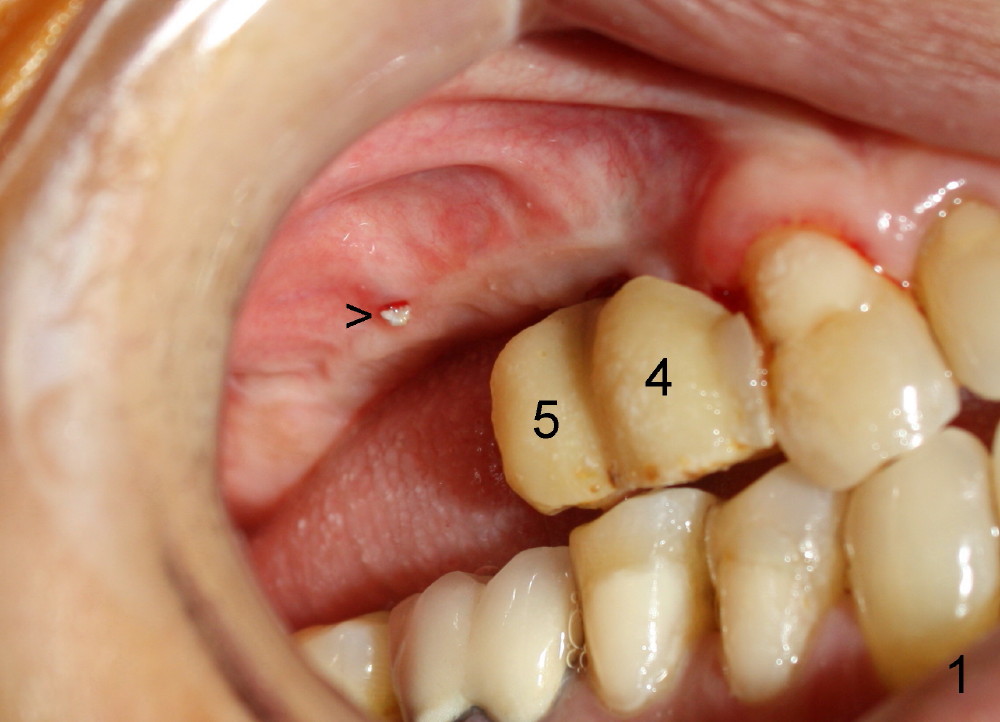

When the patient arrives at the office for sinus graft, the most important thing for her is to have two provisionals in the premolar region postop (Fig.1: #4,5; >: suture left from previous surgery). These existing provisionals appear to interfere with sinus lateral window incision and removed. So is the mini-implant.